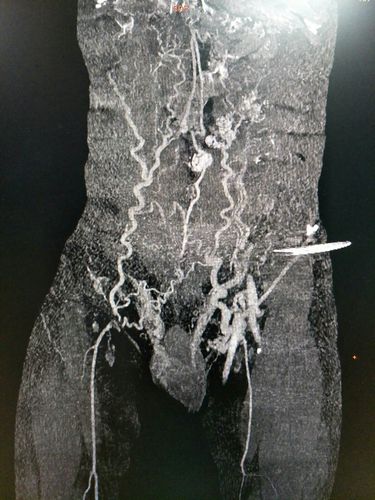

腹壁静脉曲张图片,腹壁曲张静脉

腹壁侧枝形成,右侧精索静脉曲张

临床可见的还有食管胃底静脉曲张,精索静脉曲张及腹壁静脉曲张等等

为什么肝硬化会出现腹壁静脉曲张

腹壁静脉曲张症状图片

腹壁静脉曲张